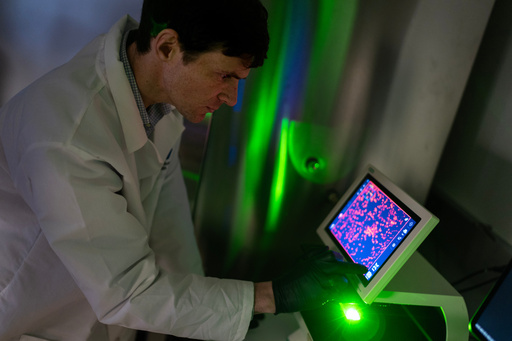

Nearby in another Hopkins lab, biomedical engineer Jordan Green is crafting a way for the immune system to reprogram itself with the help of instructions delivered by messenger RNA, or mRNA, the genetic code used in COVID-19 vaccines.

In Green's lab, a computer screen shines with brightly colored dots that resemble a galaxy. It’s a biological map that shows insulin-producing cells in the pancreas of a mouse. Red marks rogue T cells that destroy insulin production. Yellow indicates those peacemaker regulatory T cells — and they're outnumbered.

Green's team aims to use that mRNA to instruct certain immune “generals” to curb the bad T cells and send in more peacemakers. They package the mRNA in biodegradable nanoparticles that can be injected like a drug. When the right immune cells get the messages, the hope is they'd “divide, divide, divide and make a whole army of healthy cells that then help treat the disease," Green said.

The researchers will know it's working if that galaxy-like map shows less red and more yellow. Studies in people are still a few years away.